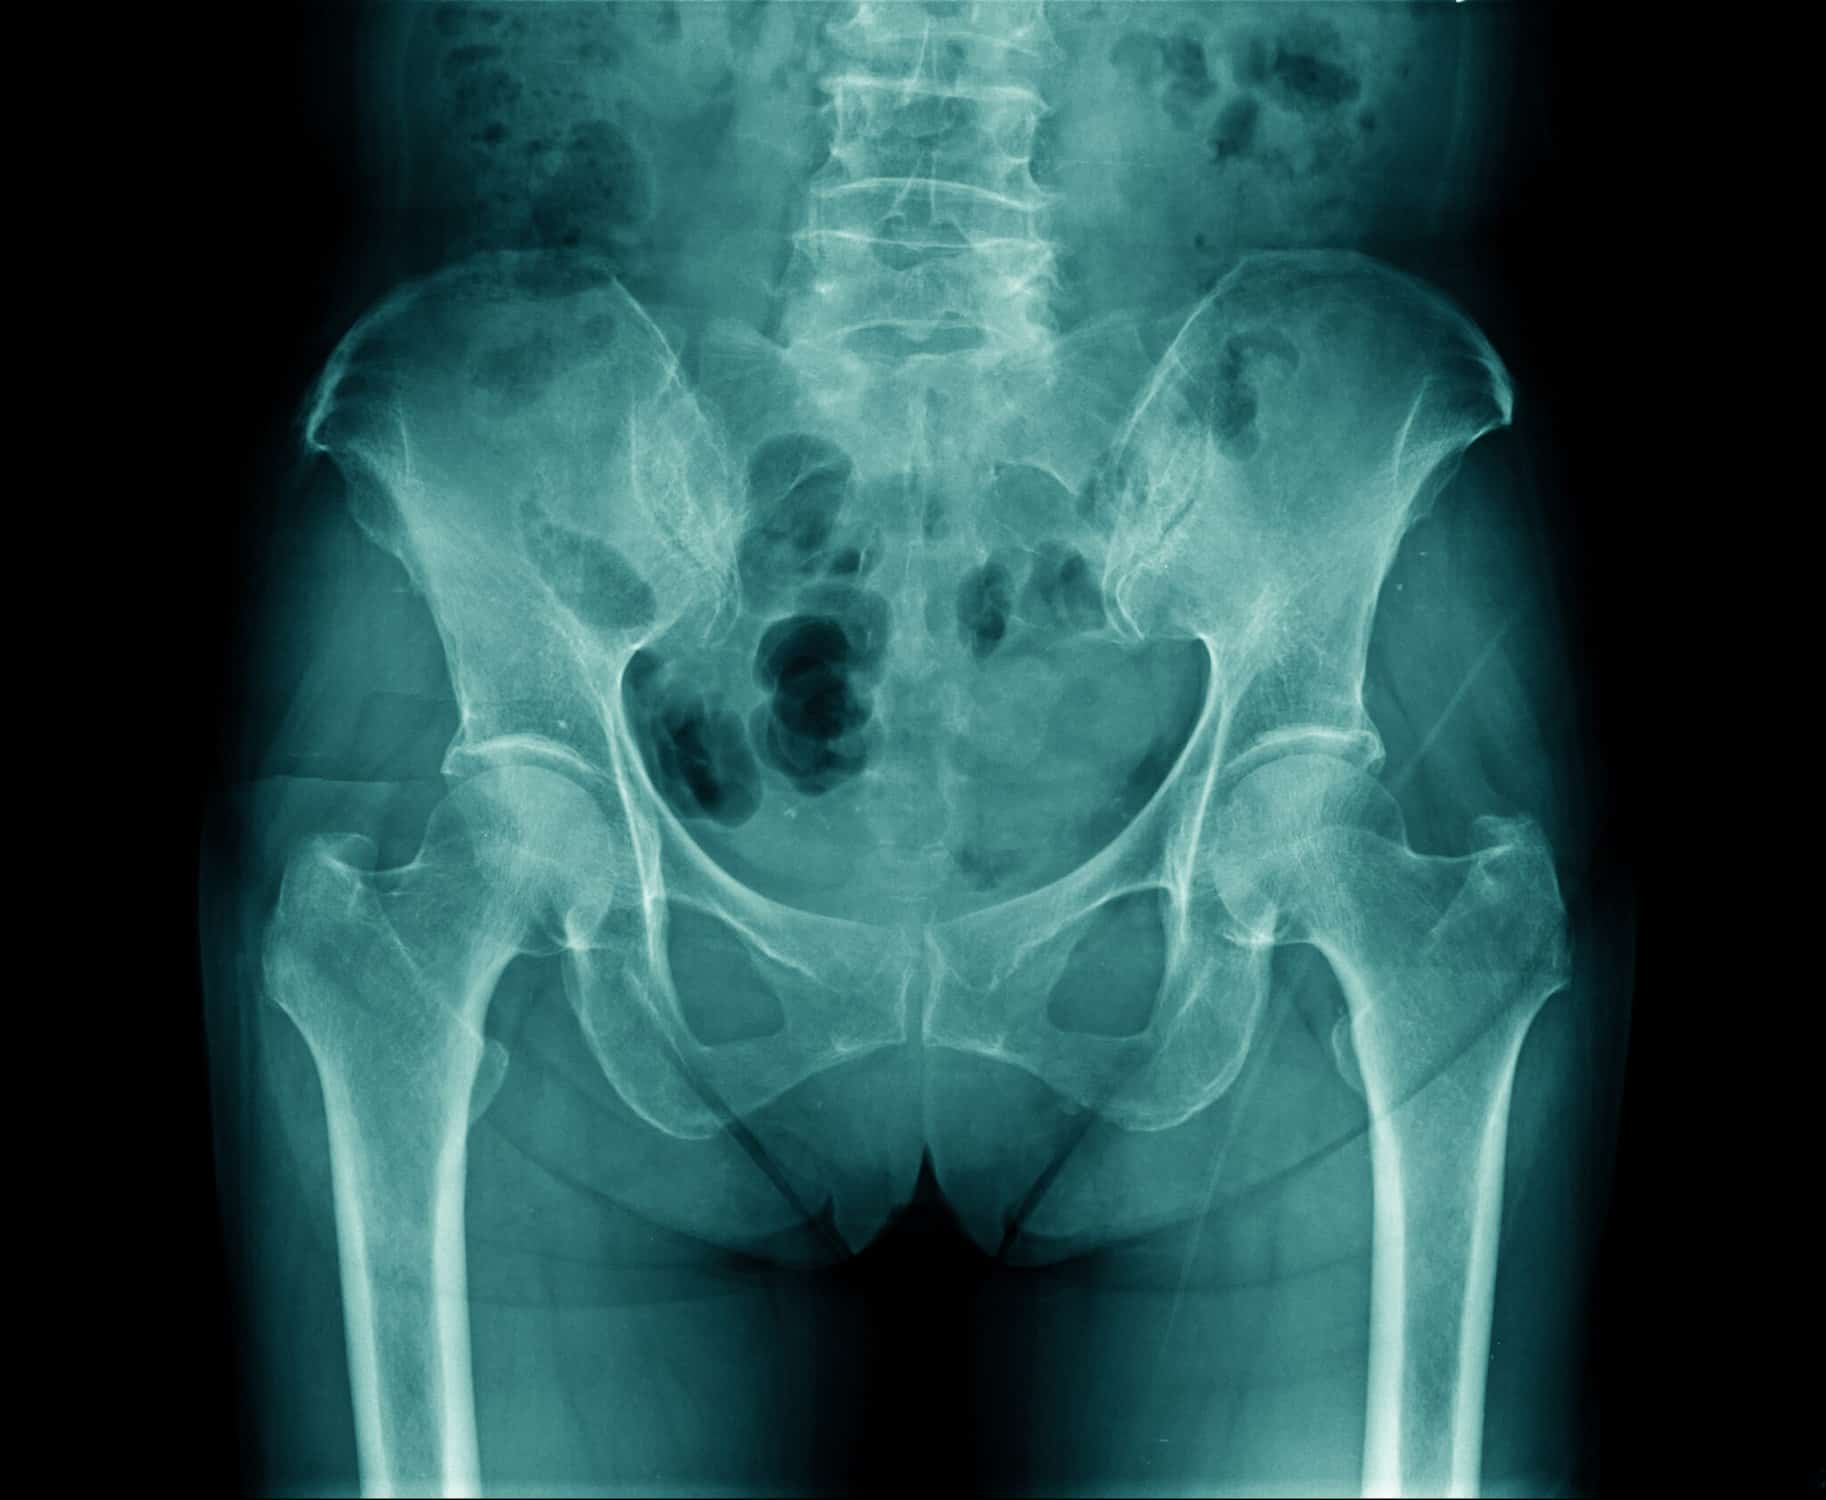

Thigh pain after total hip arthroplasty [autosaved]